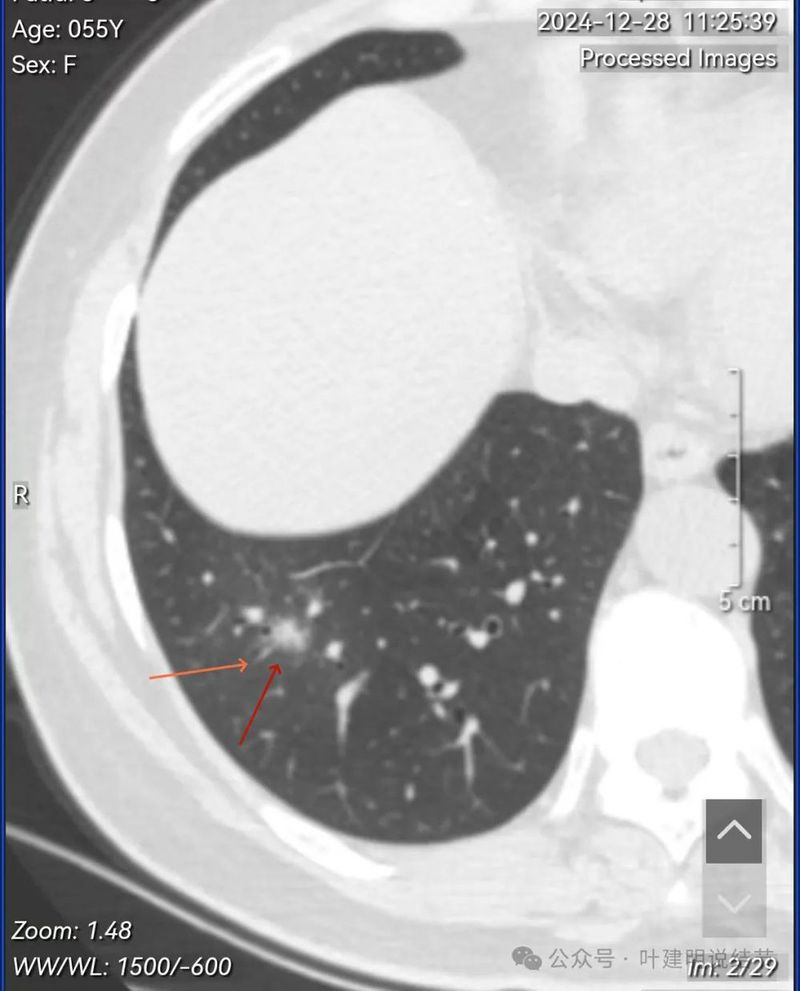

先看2024年12月28号初检查发现时的影像与报告:

右下病灶混合密度,整体轮廓较清,但瘤肺边界欠清晰。

实性成分占比高,边缘看上去有晕似的,边上有明显血管走行。也有细支气管可见。

实性部分或整体病灶缺乏收缩力,膨胀感也不明显。瘤肺边界欠清晰,感觉有一圈晕。

晕征上图更明显,进入的血管未见明显异常增粗,略显弯曲。